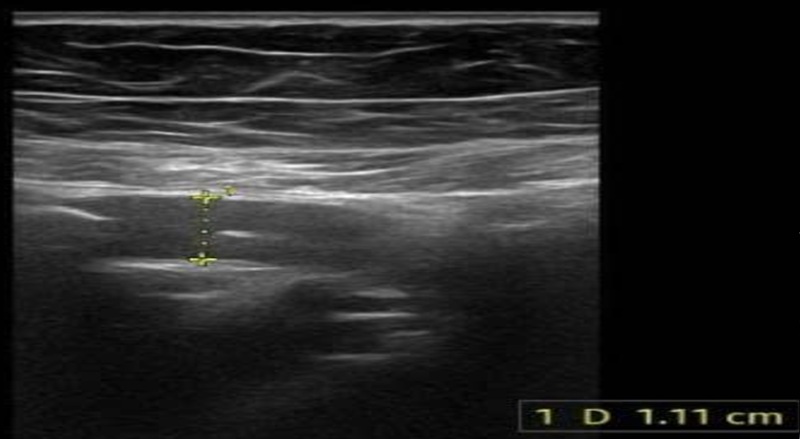

Siêu âm bụng ghi nhận, có 1 thai khoảng 12 tuần trong buồng tử cung. Ruột thừa vùng hố chậu phải có đường kính 11 mm, không xẹp khi đè, kèm hình ảnh thâm nhiễm mỡ xung quanh. Xét nghiệm máu, tình trạng viêm rõ rệt với số lượng bạch cầu tăng 15 G/L, tỷ lệ bạch cầu trung tính 88,8% và chỉ số CRP tăng 19,19 mg/L.

Siêu âm phát hiện ruột thừa ở vùng hố chậu phải, có đường kính khoảng 11mm